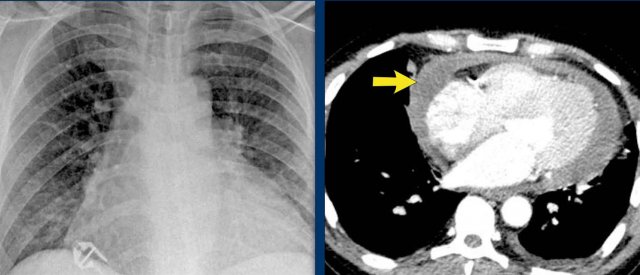

Pericardial effusion

When encountering an enlarged cardiac silhouette on chest radiography, it is essential to consider pericardial effusion as a potential mimic of cardiomegaly.

Case Example 1: Pericardial Effusion Mimicking Cardiomegaly

• On the chest radiograph, the patient appears to have a dilated heart.

• However, CT imaging clearly demonstrates that the apparent enlargement is due to significant pericardial fluid accumulation, not true myocardial chamber enlargement.

Postoperative Pericardial Hemorrhage

In patients with recent cardiac surgery, a sudden change in heart size on chest X-ray should raise suspicion for pericardial bleeding, which may be life-threatening.

Case Example 2:

• A postoperative patient showed a change in the cardiac silhouette.

• Echocardiography detected only a minimal pericardial effusion.

Case Example 2 - CT imaging

• CT imaging revealed a large posterior pericardial effusion compressing the left ventricle (blue arrow: effusion; red arrow: compressed, contrast-filled left ventricle).

• Surgical exploration confirmed a large posterior pericardial hematoma.

Note

: Minimal anterior fluid on ultrasound may underestimate the true volume if the effusion is loculated posteriorly, highlighting the value of CT in postoperative cases.

Especially in patients who had recent cardiac surgery an enlargement of the heart figure can indicate pericardial bleeding.

This patient had a change in the heart configuration (importance of prior imaging) and pericardial bleeding was suspected.

Ultrasound demonstrated only a minimal pericardial effusion.

Case Example 3: Valve Replacement & Heart Failure

Post-valve replacement, a patient presents with a markedly enlarged cardiac silhouette on chest X-ray.

Findings

• A large cardiac silhouette

• There is evidence of pulmonary vascular redistribution, suggesting congestive heart failure.

Case Example 3: CT imaging

CT demonstrates a large pericardial effusion.

Tip

Always compare postoperative chest films with preoperative imaging to detect interval changes such as effusions or evolving heart failure.